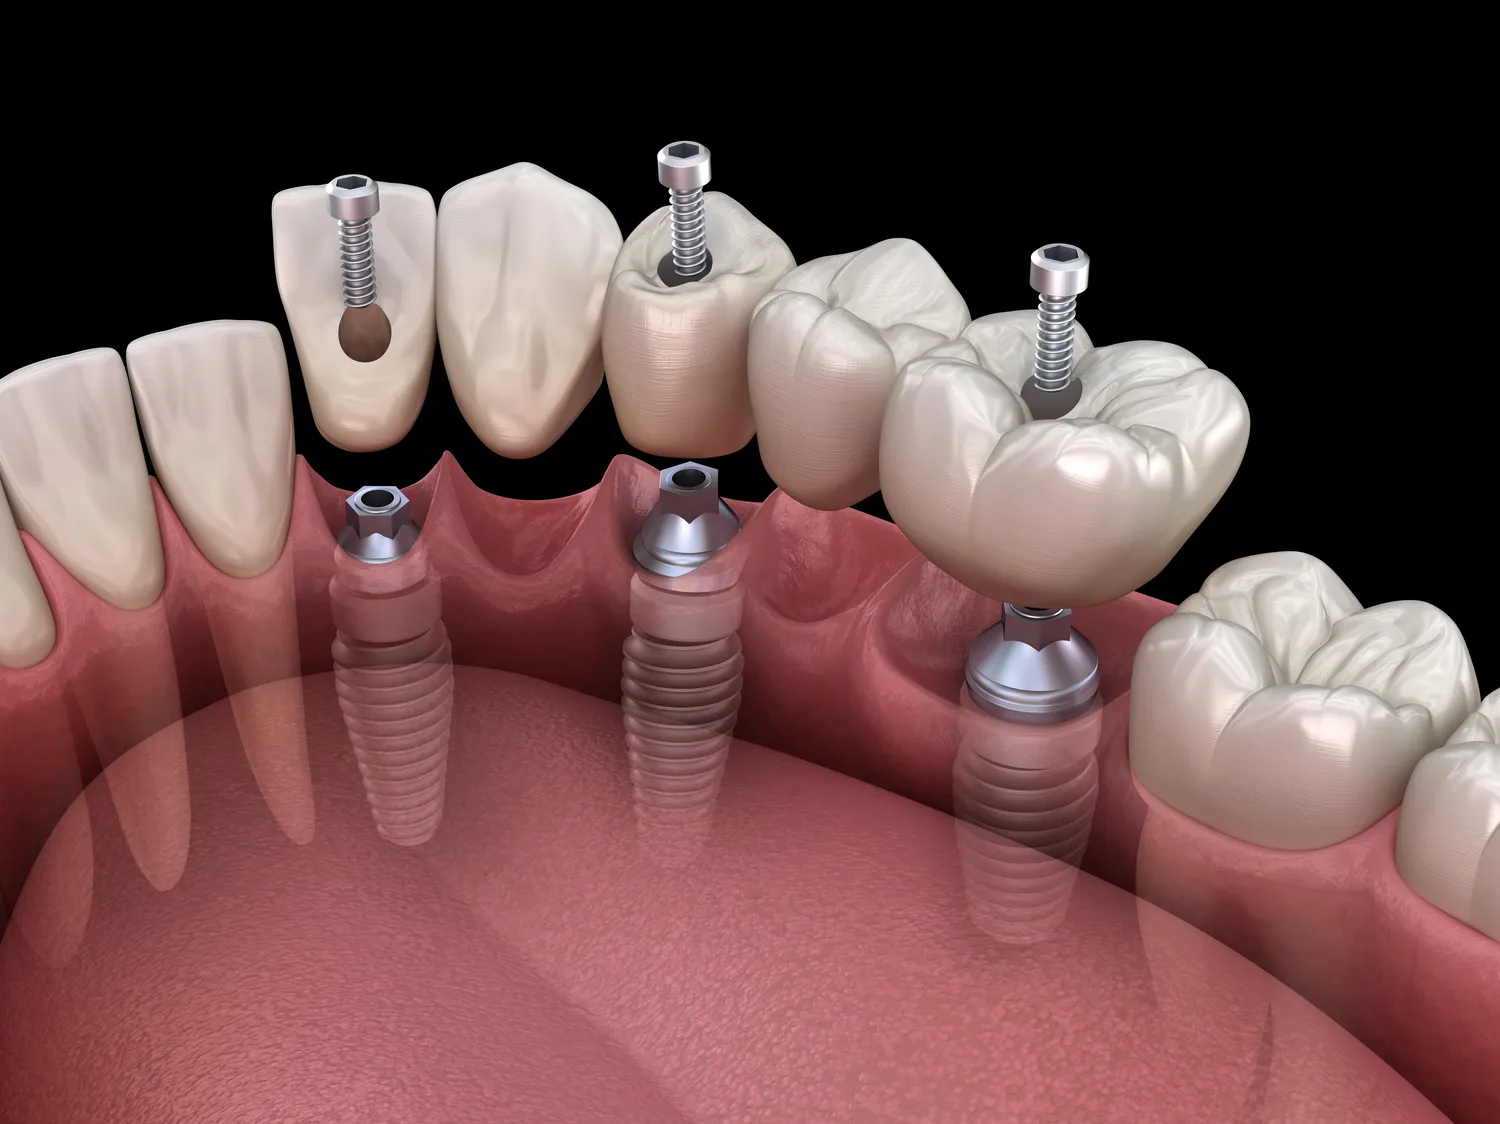

Implanty zębów to popularne rozwiązanie w stomatologii, które pozwala na odbudowę brakujących zębów. Jednak nie każdy pacjent może skorzystać z tej metody leczenia. Istnieje wiele przeciwwskazań, które mogą uniemożliwić przeprowadzenie zabiegu. Przede wszystkim, jednym z najważniejszych czynników jest stan zdrowia pacjenta. Osoby cierpiące na choroby przewlekłe, takie jak cukrzyca, mogą mieć zwiększone ryzyko powikłań pooperacyjnych. Ponadto, choroby serca oraz problemy z krzepliwością krwi również mogą być istotnymi przeszkodami w zakwalifikowaniu się do zabiegu. Kolejnym istotnym aspektem są nawyki pacjenta, takie jak palenie papierosów, które negatywnie wpływają na proces gojenia się tkanek oraz integrację implantu z kością.

Proces gojenia po wszczepieniu implantów zębowych jest kluczowym etapem, który wpływa na ostateczny sukces zabiegu. Po wszczepieniu implantu następuje okres osseointegracji, czyli integracji implantu z kością szczęki lub żuchwy. Ten proces trwa zazwyczaj od kilku tygodni do kilku miesięcy, w zależności od indywidualnych predyspozycji pacjenta oraz jakości kości. W tym czasie ważne jest przestrzeganie zaleceń lekarza dotyczących higieny jamy ustnej oraz unikania nadmiernego obciążania implantu. Pacjenci mogą doświadczać pewnego dyskomfortu lub bólu w okolicy zabiegu, dlatego lekarz często zaleca stosowanie leków przeciwbólowych oraz zimnych okładów na obszarze operowanym. Regularne wizyty kontrolne u stomatologa są niezbędne do monitorowania procesu gojenia oraz oceny stanu implantu. Po zakończeniu procesu osseointegracji można przystąpić do dalszych etapów leczenia, takich jak osadzenie korony protetycznej na implancie.